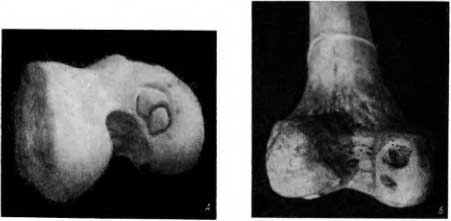

На медиальном мыщелке бедренной кости из погребения в старой Вятке мы обнаружили 2 полуотделившихся участка кости, находившихся в одном ложе (в одной ямке) почти овальной или бобовидной формы. Оба костных образования между собой не были связаны, их отделял довольно глубокий ров. Вместе они напоминали восьмерку (рис. 50, А).

Рис. 50. А — частичный остеолиз, или рассекающий остеохондрит; фаза, предшествующая отторжению; Б — частичный остеохондролиз, или рассекающий остеохондрит, после отторжения двух фрагментов.

Таким образом, рентгенологически можно было ошибочно трактовать как нишу (ямку) круговой ров, напоминающий восьмерку (рис. 50, А). Этот ров лишь подрывал один участок кости в большей, другой — в меньшей мере. Полного отторжения не было.

Второе наблюдение (также из погребения в старой Вятке) представляет интерес в том отношении, что на мыщелке бедренной кости имелись 2 ниши (рис. 50, Б). Обе ниши находились не на медиальном, а на латеральном мыщелке бедра, что встречается очень редко.